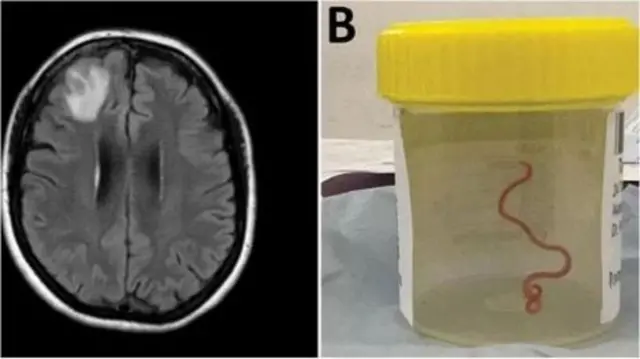

Beyində canlı soxulcan tapıldı

Şəklin mənbəyi, Avstraliya Beynəlxalq Universiteti

Dünyada ilk dəfə Avstraliyadan olan bir qadının beynindən 8 santimetr uzunluğunda bir soxulcan çıxarıldı.

“Simə oxşayan cism” ötən il Kanberra şəhərindəki xəstəxanaların birində aparılan tibbi əməliyyat zamanı tapılmışdı, lakin əməliyyatla bağlı yekun nəticə bu il ictimaiyyətə açıqlandı.

Əməliyyatı həyata keçirən həkim Hari Priya Bandi “heç gözlədiyimiz bir şey deyildi, hər kəs şok oldu” dedi.

64 yaşlı qadında aylardır davam edən mədə ağrısı, öskürək, gecə tərləməsi kimi simptomlardan sonra unutqanlıq və depressiya kimi əlamətlər də görülməyə başladı.

Qadın 2021-ci ilin yanvarında xəstəxanaya yerləşdirildi və rentgen müayinəsi zamanı beynin sağ ön hissəsində qızartı göründü.

Lakin bütün bunların səbəbi 2022-ci ilin iyununda həkim Bandinin etdiyi biopsiyadan sonra məlum oldu.

Həkimlərin fikrincə, qırmızı parazit xəstənin beynində 2 ayadək canlı qalıb.

Bunun sürfələrin insan beyninə hücumu və orada inkişafı ilə bağlı dünyada baş verən ilk hadisə olduğu güman edilir. Mütəxəsislər bu nadir hadisəni heyvanlardan insanlara keçən xətəlik və infeksiyaların artan təhlükəsi kimi şərh edirlər.